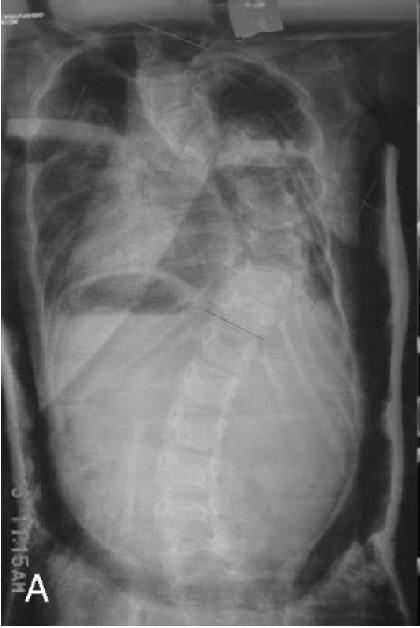

• Scoliosis (Neurofibromatosis)

• Introduction

• spine is most common site of skeletal involvement in NF-1

• can take two forms

• idiopathic-like form (nondystrophic)

• longer curve and treatment resembles that for idiopathic scoliosis

• dystrophic form

• curve is typically thoracic kyphoscoliosis with a short segmented and sharp curve with distorted ribs and vertebrae

• usually recognized earlier than nondystrophic form

• generally characterized by a sharp angular curve involving 4 to 6 vertebrae

• Imaging

• radiographs show

• vertebral scalloping

• penciling of ribs (penciling of 3 or more ribs is a poor prognostic finding and associated with rapid curve progression)

• enlarged foramina